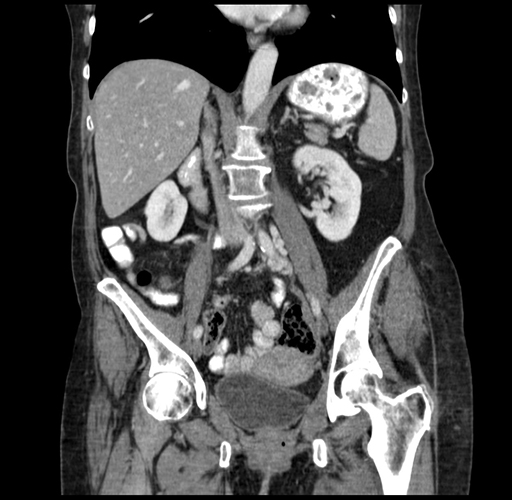

Pre-Chemo: Coronal Venous

Coronal Venous